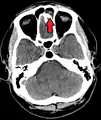

| A CT scan showing sinusitis of the ethmoid sinus | |

Frontal sinusitis